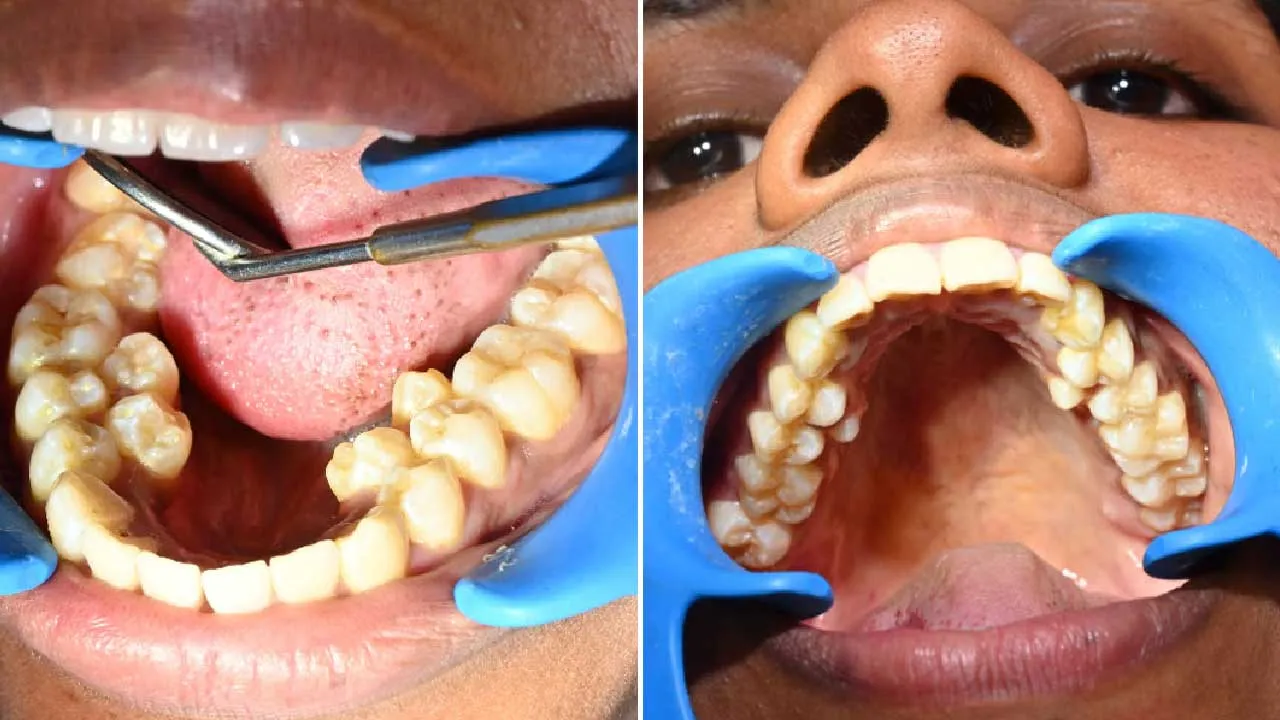

ભારતમાં એક અનોખો વિશ્વ રેકોર્ડ બન્યો છે. કલ્પના બાલન નામની 26 વર્ષની મહિલાના મોઢામાં કુલ 38 દાંત છે, જે સામાન્ય માણસ કરતાં 6 વધુ છે. આ કારણે તેમનું નામ Guinness World Records માં નોંધાયું છે. કોઇ વ્યક્તિના મોઢામાં વધારે દાંત હોય તો શું તે પડાવી દેવા જોઇએ કે રાખવામાં કોઇ વાંધો નથી.

સામાન્ય રીતે એક યુવાન વ્યક્તિના મોઢામાં 32 દાંત હોય છે. પરંતુ કલ્પના બાલનના મોઢામાં 4 વધારાના દાંત નીચેના જડબામાં અને 2 વધારાના દાંત ઉપરના જડબામાં છે. તેમના વધારાના દાંત કિશોરાવસ્થામાં ધીમે-ધીમે ઉગવા લાગ્યા હતા. તેમને ખાસ પીડા તો નથી, પરંતુ ખોરાક ખાતી વખતે ઘણીવાર ખોરાક દાંત વચ્ચે ફસાઈ જાય છે.

આ સ્થિતિને Hyperdontia અથવા supernumerary teeth કહેવામાં છે. આમાં સામાન્ય કરતાં વધુ દાંત વિકસે છે. વિશ્વના લગભગ 3–4% લોકોમાં આ સમસ્યા જોવા મળે છે.